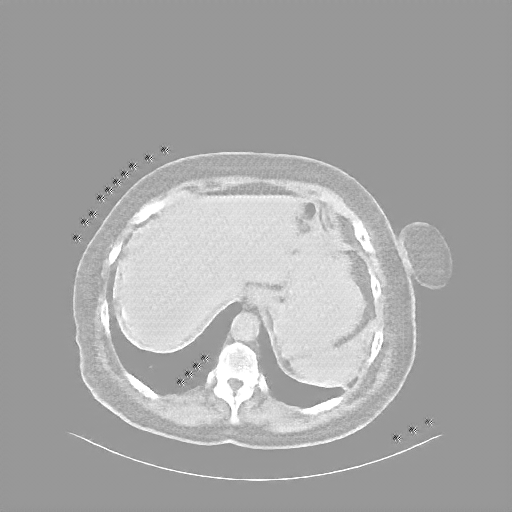

Original NATIVE CT scan (input)

Full window (WL 1023.5, WW 4095 β†’ Low βˆ’1024, High +3071)

Actual HU range: [-160.0, 240.0]

Lung window (WL -600, WW 1500 β†’ Low βˆ’1350, High +150)

Actual HU range: [-160.0, 150.0]

Mediastinum window (WL 40, WW 400 β†’ Low βˆ’160, High +240)